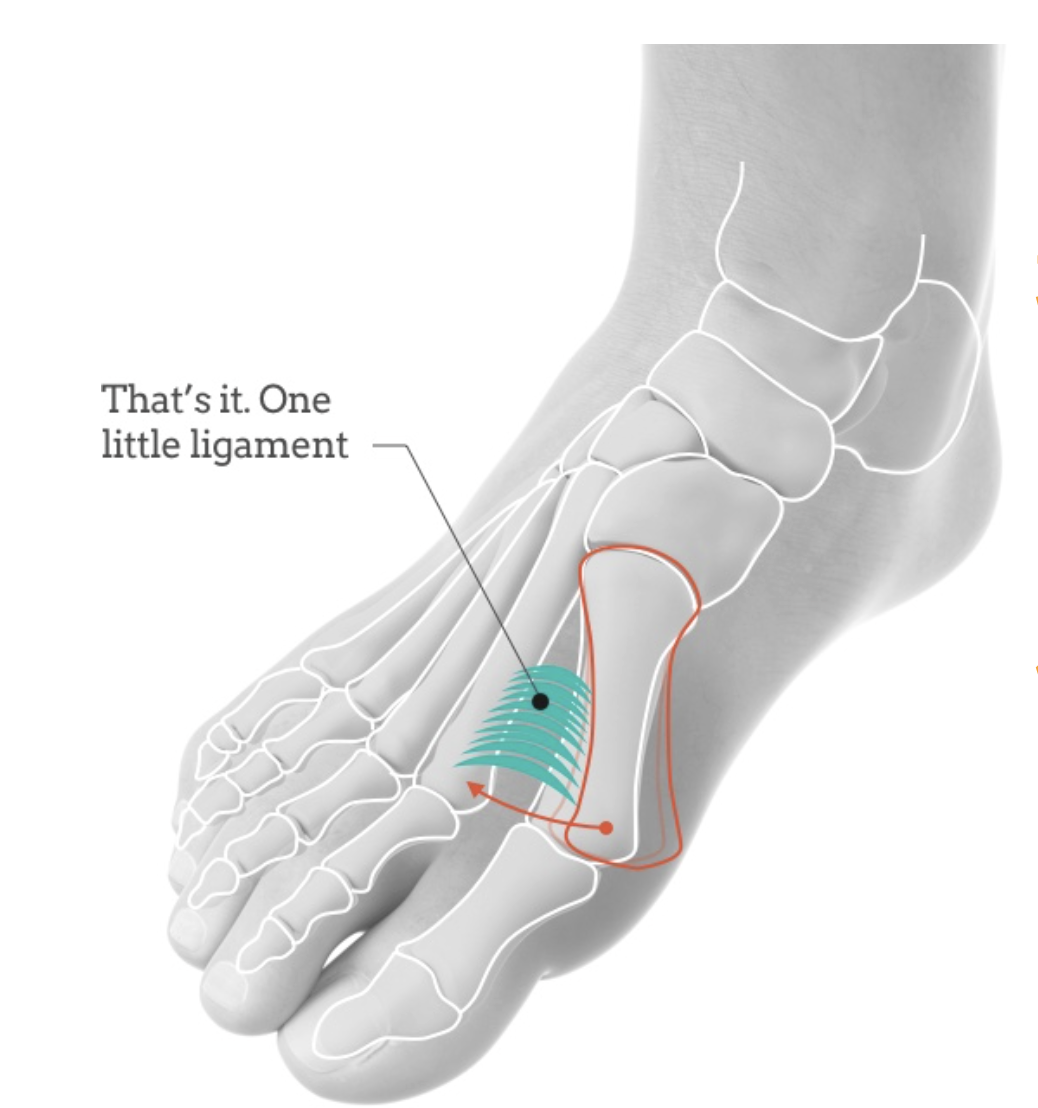

韧带联合术的手术原理围绕“复位、固定、稳定”三大核心展开,基于对拇外翻病理机制的深刻理解——MPV作为拇外翻的潜在病因,其本质是第一跖骨稳定性韧带功能不全,导致第一跖骨向内侧移位、与第二跖骨分离,进而引发拇趾外侧偏斜。因此,韧带联合术的核心目标是恢复第一跖骨的正常力线,重建其与第二跖骨的稳定性,同时松解外侧挛缩软组织,实现拇外翻畸形的矫正。

▲图示第一跖骨内翻(MPV)畸形跖骨远端冠状面示意图,显示第一跖骨向内侧移位、第一跖骨间距离增宽,以及因系杆系统最内侧端的跖籽内侧韧带松弛和延长而导致的籽骨外侧半脱位。